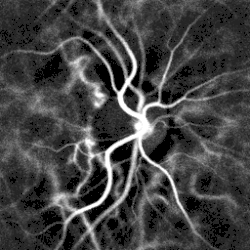

Optical measurements

Pulse oximetry of the finger and laser Doppler imaging of the eye fundus are often used in the clinics. Those techniques can assess the heart rate by measuring the delay between pulses.